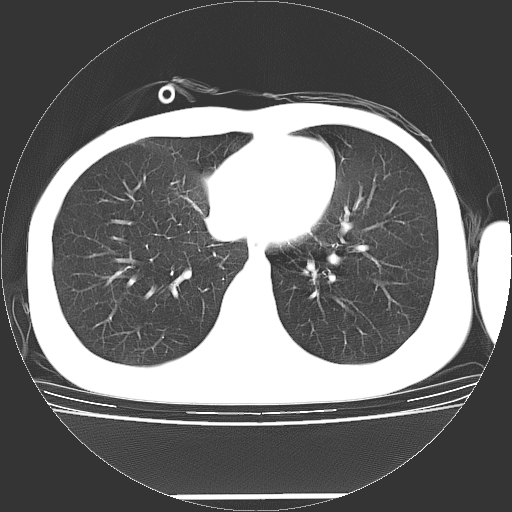

标题: CT19767:男,20岁,右侧气胸行闭式引流术后五天CT检查。 [打印本页]

男,20岁,右侧气胸行闭式引流术后五天ct检查看肺内是否有肺大泡,纵隔窗未见异常,未上传。

1)右侧胸腔闭式引流术后导管留置。2)右肺未见肺大泡。

未见肺大泡,还有微量气体。